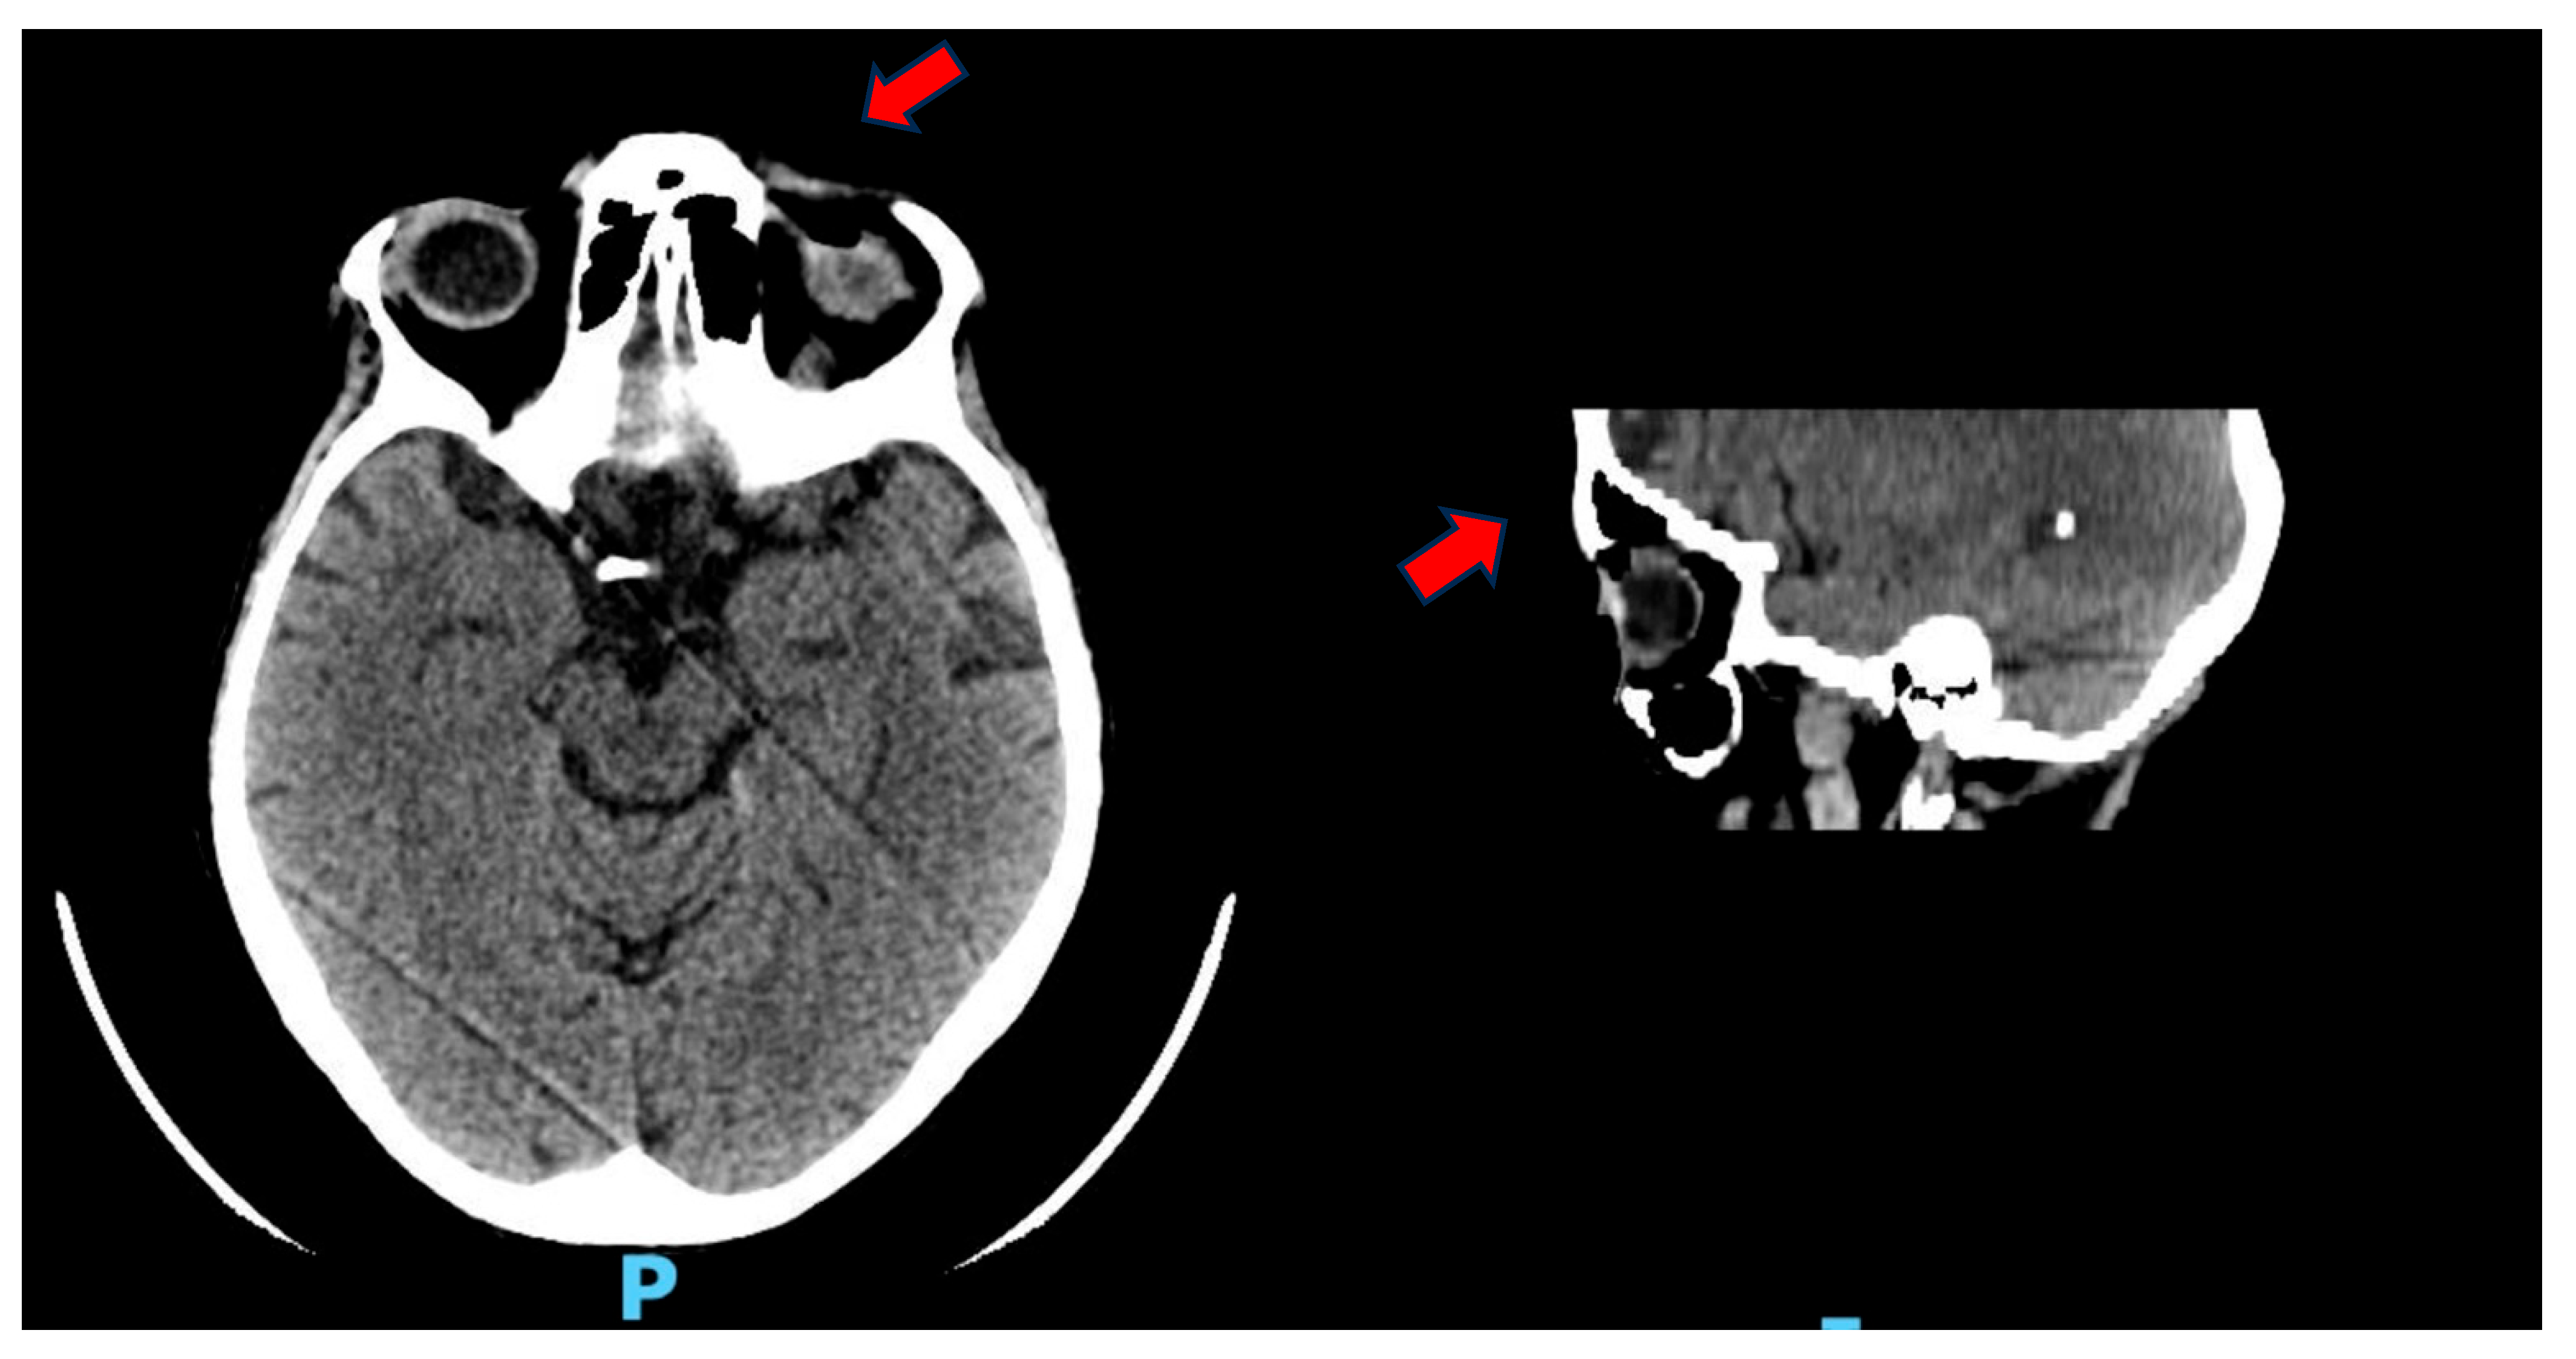

Three weeks later, however, the patient underwent ocular evisceration due to corneal perforation secondary to corneal melting. HLA typing (including HLA-A29, HLA-B27, and HLA-DR4) was not performed. Corneal scraping and culture were also not carried out prior to surgical intervention. Due to persistent diarrhea and the suspicion of a toxic megacolon, an abdominal CT was performed, revealing intestinal pneumatosis with signs of vascular hypoperfusion in the transverse colon (Figure 2). An exploratory laparoscopy was performed, but there was no evidence of ischemic damage.

Figure 2. CT scan with contrast medium: hypoperfused appearance of the walls of the transverse colon, with the presence of free air in the context of the walls and around the viscera, as in intestinal pneumatosis.